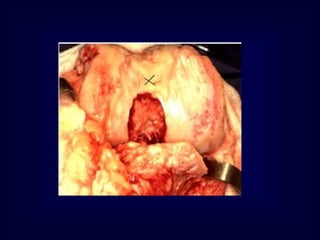

AFTER ARTHROTOMY

STEP 1 : REMOVAL OF OSTEOPHYTES UNDER MCL

STEP 2 : CLEARING FEMORAL NOTCH

STEP 3 : REMOVAL OF INFRAPATELLAR PAD OF FAT

STEP 4 : CLEARING SUPRAPATELLAR SYNOVIUM

STEP 5- Inverted Isosceles Triangle

STEP 6 : CLEARING OF

PATELLOFEMORAL OSTEOPHYTES

+ DEBULKING